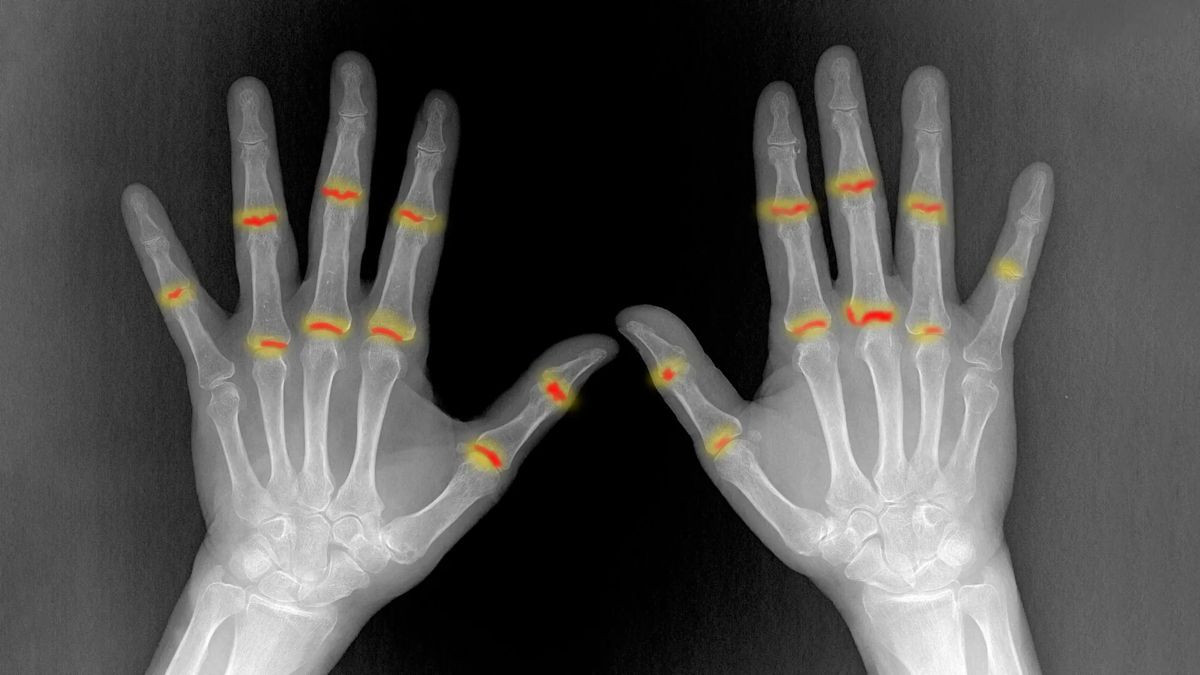

Για πολλά χρόνια η επιστημονική κοινότητα γνώριζε ότι η ψωρίαση δεν περιορίζεται μόνο στην επιφάνεια του δέρματος. Ένα σημαντικό ποσοστό ασθενών, περίπου το 30%, αναπτύσσει τελικά ψωριασική αρθρίτιδα, μια επώδυνη και συχνά μη αναστρέψιμη φλεγμονώδη πάθηση. Το ερώτημα που παρέμενε αναπάντητο, ωστόσο, ήταν το «γιατί». Γιατί ορισμένοι ασθενείς εμφανίζουν αρθρίτιδα ενώ άλλοι όχι; Και πώς ακριβώς μεταδίδεται η φλεγμονή από το δέρμα στις αρθρώσεις;

Στους ασθενείς που αναπτύσσουν ψωριασική αρθρίτιδα, αυτός ο μηχανισμός ασφαλείας καταρρέει. Οι ινοβλάστες παρουσιάζουν δυσλειτουργία και αδυνατούν να ελέγξουν τους εισβολείς. Ως αποτέλεσμα, τα μυελοειδή κύτταρα ενεργοποιούνται ανεξέλεγκτα, προκαλώντας τη φλεγμονώδη αντίδραση που οδηγεί σε πόνο και καταστροφή της άρθρωσης.